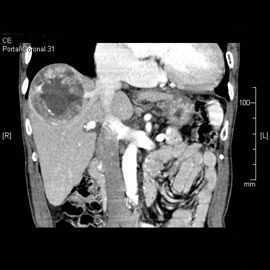

CT検査は体内における各臓器、組織のX線透過量の違いをデータとして収集し、コンピュータで断面像にしています。また、この断面像を細かく収集し積み重ねて画像処理をすることにより、任意の角度から観察することが出来るMPR画像や、3D構築画像を得ることも出来ます。さらに造影剤を使用することによって、血管の3D画像も容易に得ることが出来ます。